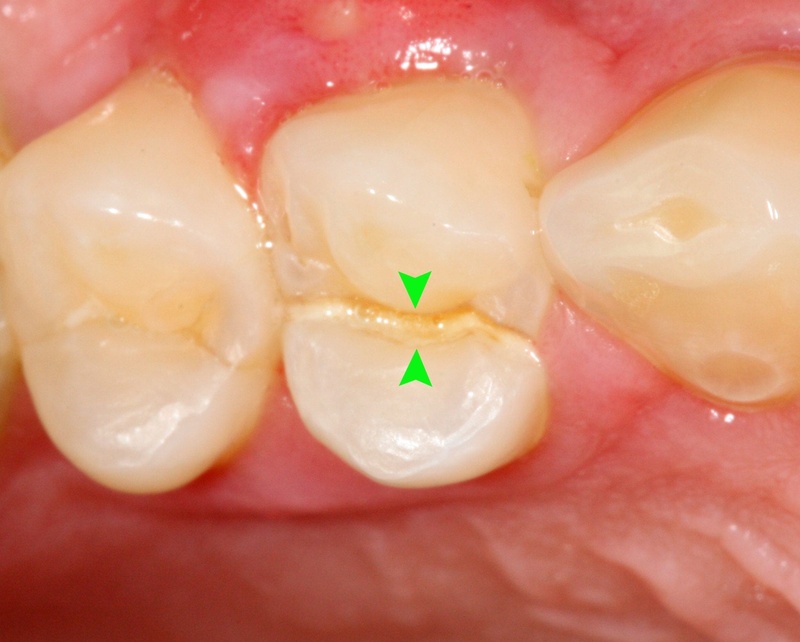

Nứt dọc thân răng là một đường nứt chạy từ mặt nhai xuống chân răng. Đường nứt này có thể lan xuống dưới đường viền nướu, thậm chí sâu vào trong chân răng, thường gây tổn thương mô mềm bên trong răng.

- Vết nứt có thể nhìn thấy: Một số trường hợp có thể nhìn thấy vết nứt bằng mắt thường trên thân răng.